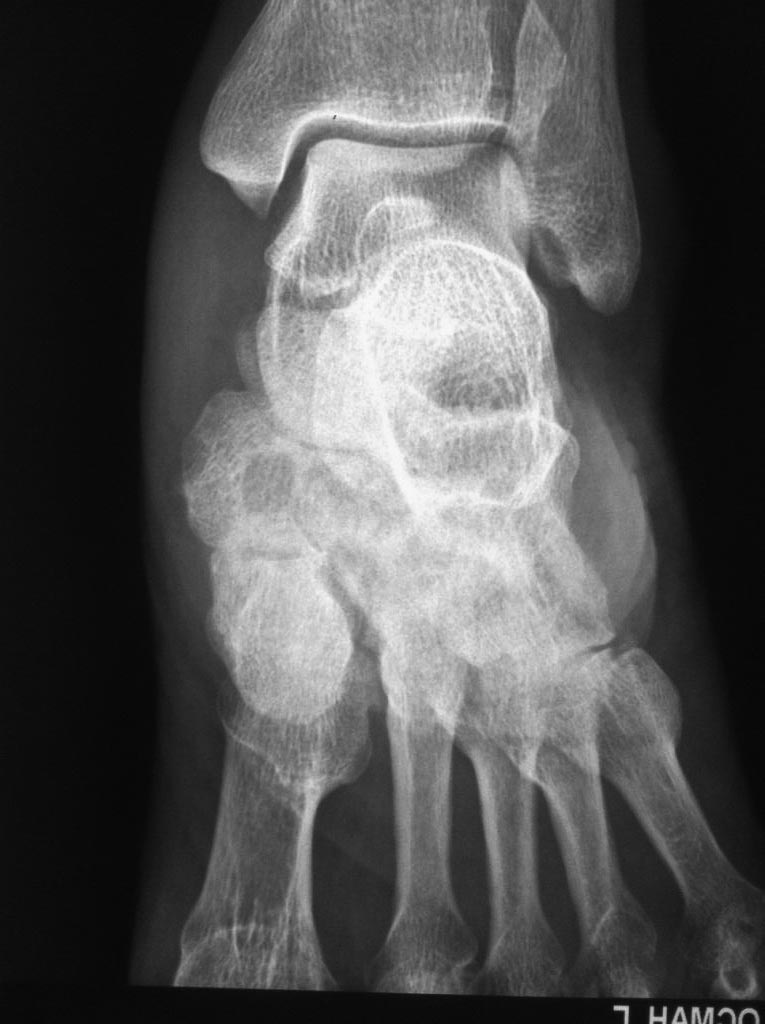

[Ortho] Асептический некроз костей среднего отдела стоп.

Доброго времени суток. Обратился пациент, 62 года, бытовые и трудовые

условия в данное время не отягощены и не были никогда тяжелыми, без

вредных привычек, со слов оперативных вмешательств не было, курсов

гормональной терапии не получал, периодически принимает лекарственные

препараты от арт. гипертензии. Без видимых причин около 1 года назад

появились боли в стопах при ходьбе и нагрузке, в связи с чем обратился к

ортопеду.

Лаб исследования: Ревмофактор, С-реакт. белок, АЦЦП, Мочевая кислота и

др. в пределах возрастной нормы. Хотелось бы услышать мнения. Заранее

благодарен.

Вложение не в текстовом формате было извлечено…

Имя     : IMG_5004.jpg

Тип     : image/jpeg

Размер  : 91799 байтов

Описание: отсутствует

Url     : http://weborto.net:8080/pipermail/ortho/attachments/20141117/cf23b1b3/attachment-0005.jpg